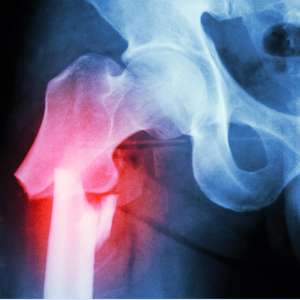

What is a Fracture?

- Fractures are the same as a “broken bones” and often occur due to a high energy injuries or fall, however sometimes they can occur through minor incidents if the bone has been weakened for some reason such as osteoporosis or stress fractures can occur from repetitive trauma.

- Sometimes to ensure the fracture can heal in an optimal position or allow early mobilisation surgical fixation is required.

- Fractures of the clavicle, forearm, hip, knee, ankle and foot all require an individualised approach to their treatment plan and depend on injury and patient factors.